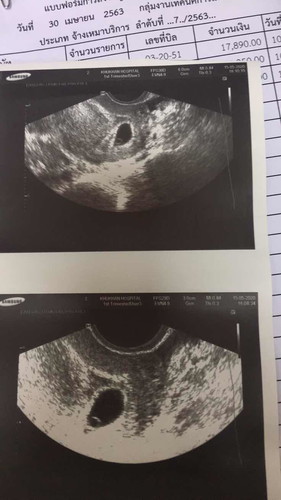

6 week HCG=56,901 น่ากังวลไหม

ยังไม่พบหัวใจเต้นค่ะ กลัวไข่ฝ่อ เคยท้องลมด้วยค่ะ

VIP Parentsยังไม่พบหัวใจเต้นค่ะ กลัวไข่ฝ่อ เคยท้องลมด้วยค่ะ